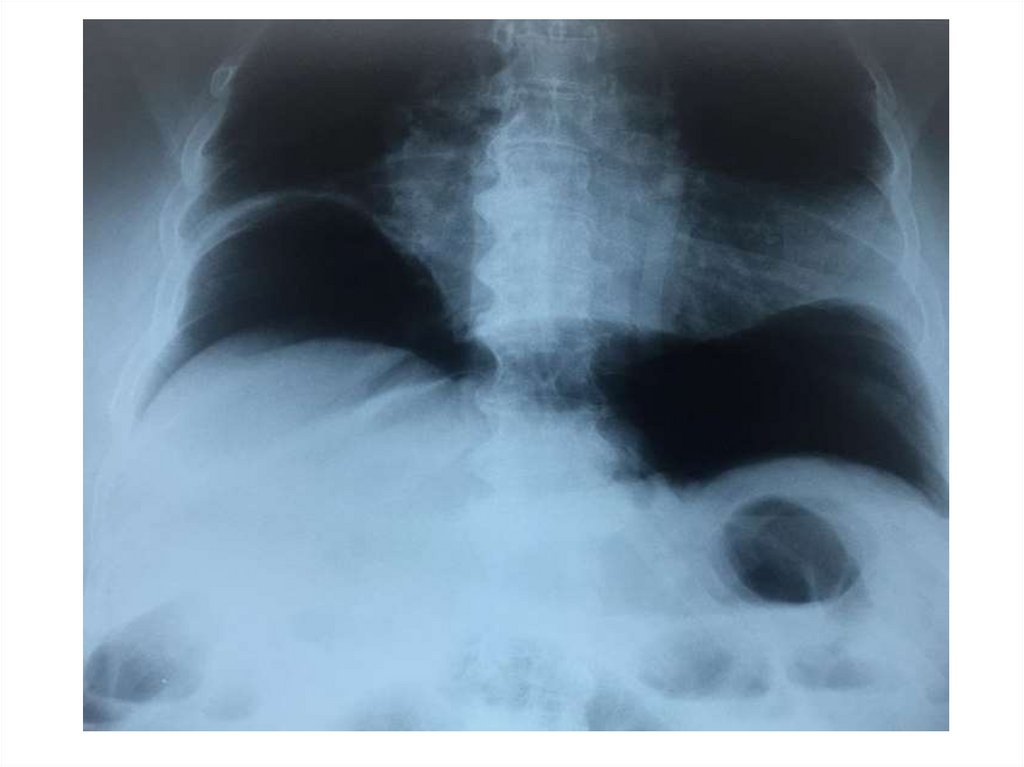

На рентгенограмме грудного отдела

позвоночника в прямой проекции стоя

определяется отклонение оси

позвоночника вправо с

формированием сколиотической дуги

на уровне Th6-Th11, угол сколиоза 1100

(4 степень сколиоза)

На рентгенограммах грудного и поясничного отделов позвоночника в

двух проекциях лёжа отклонение оси позвоночника влево на уровне Th4Th12, угол сколиоза 650 (4 степень сколиоза) с правосторонней

противодугой на уровне Th12-L4, угол сколиоза 450. Признаки

патологической ротации тел позвонков 4 степени. Грудной кифоз усилен

(угол кифоза 720). Вентральная клиновидность тел грудных позвонков на

высоте кифоза. Снижение высоты межпозвонковых дисков.